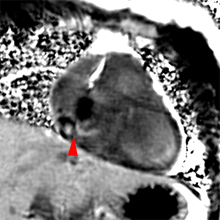

– Les abcès annulaires infectieux ou froids calcifiés constituent de bonnes indications pour l’IRM cardiaque.

– L’IRM est un complément intéressant dans les suspicions de fibroélastomes (mais moins performant que l’ETO).